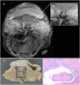

Primary spinal tumor

Spinal tumors are neoplasms located in either the vertebral column or the spinal cord. There are three main types of spinal tumors classified based on their location: extradural and intradural (intradural-intramedullary and intradural-extramedullary). [Source: Wikipedia ]